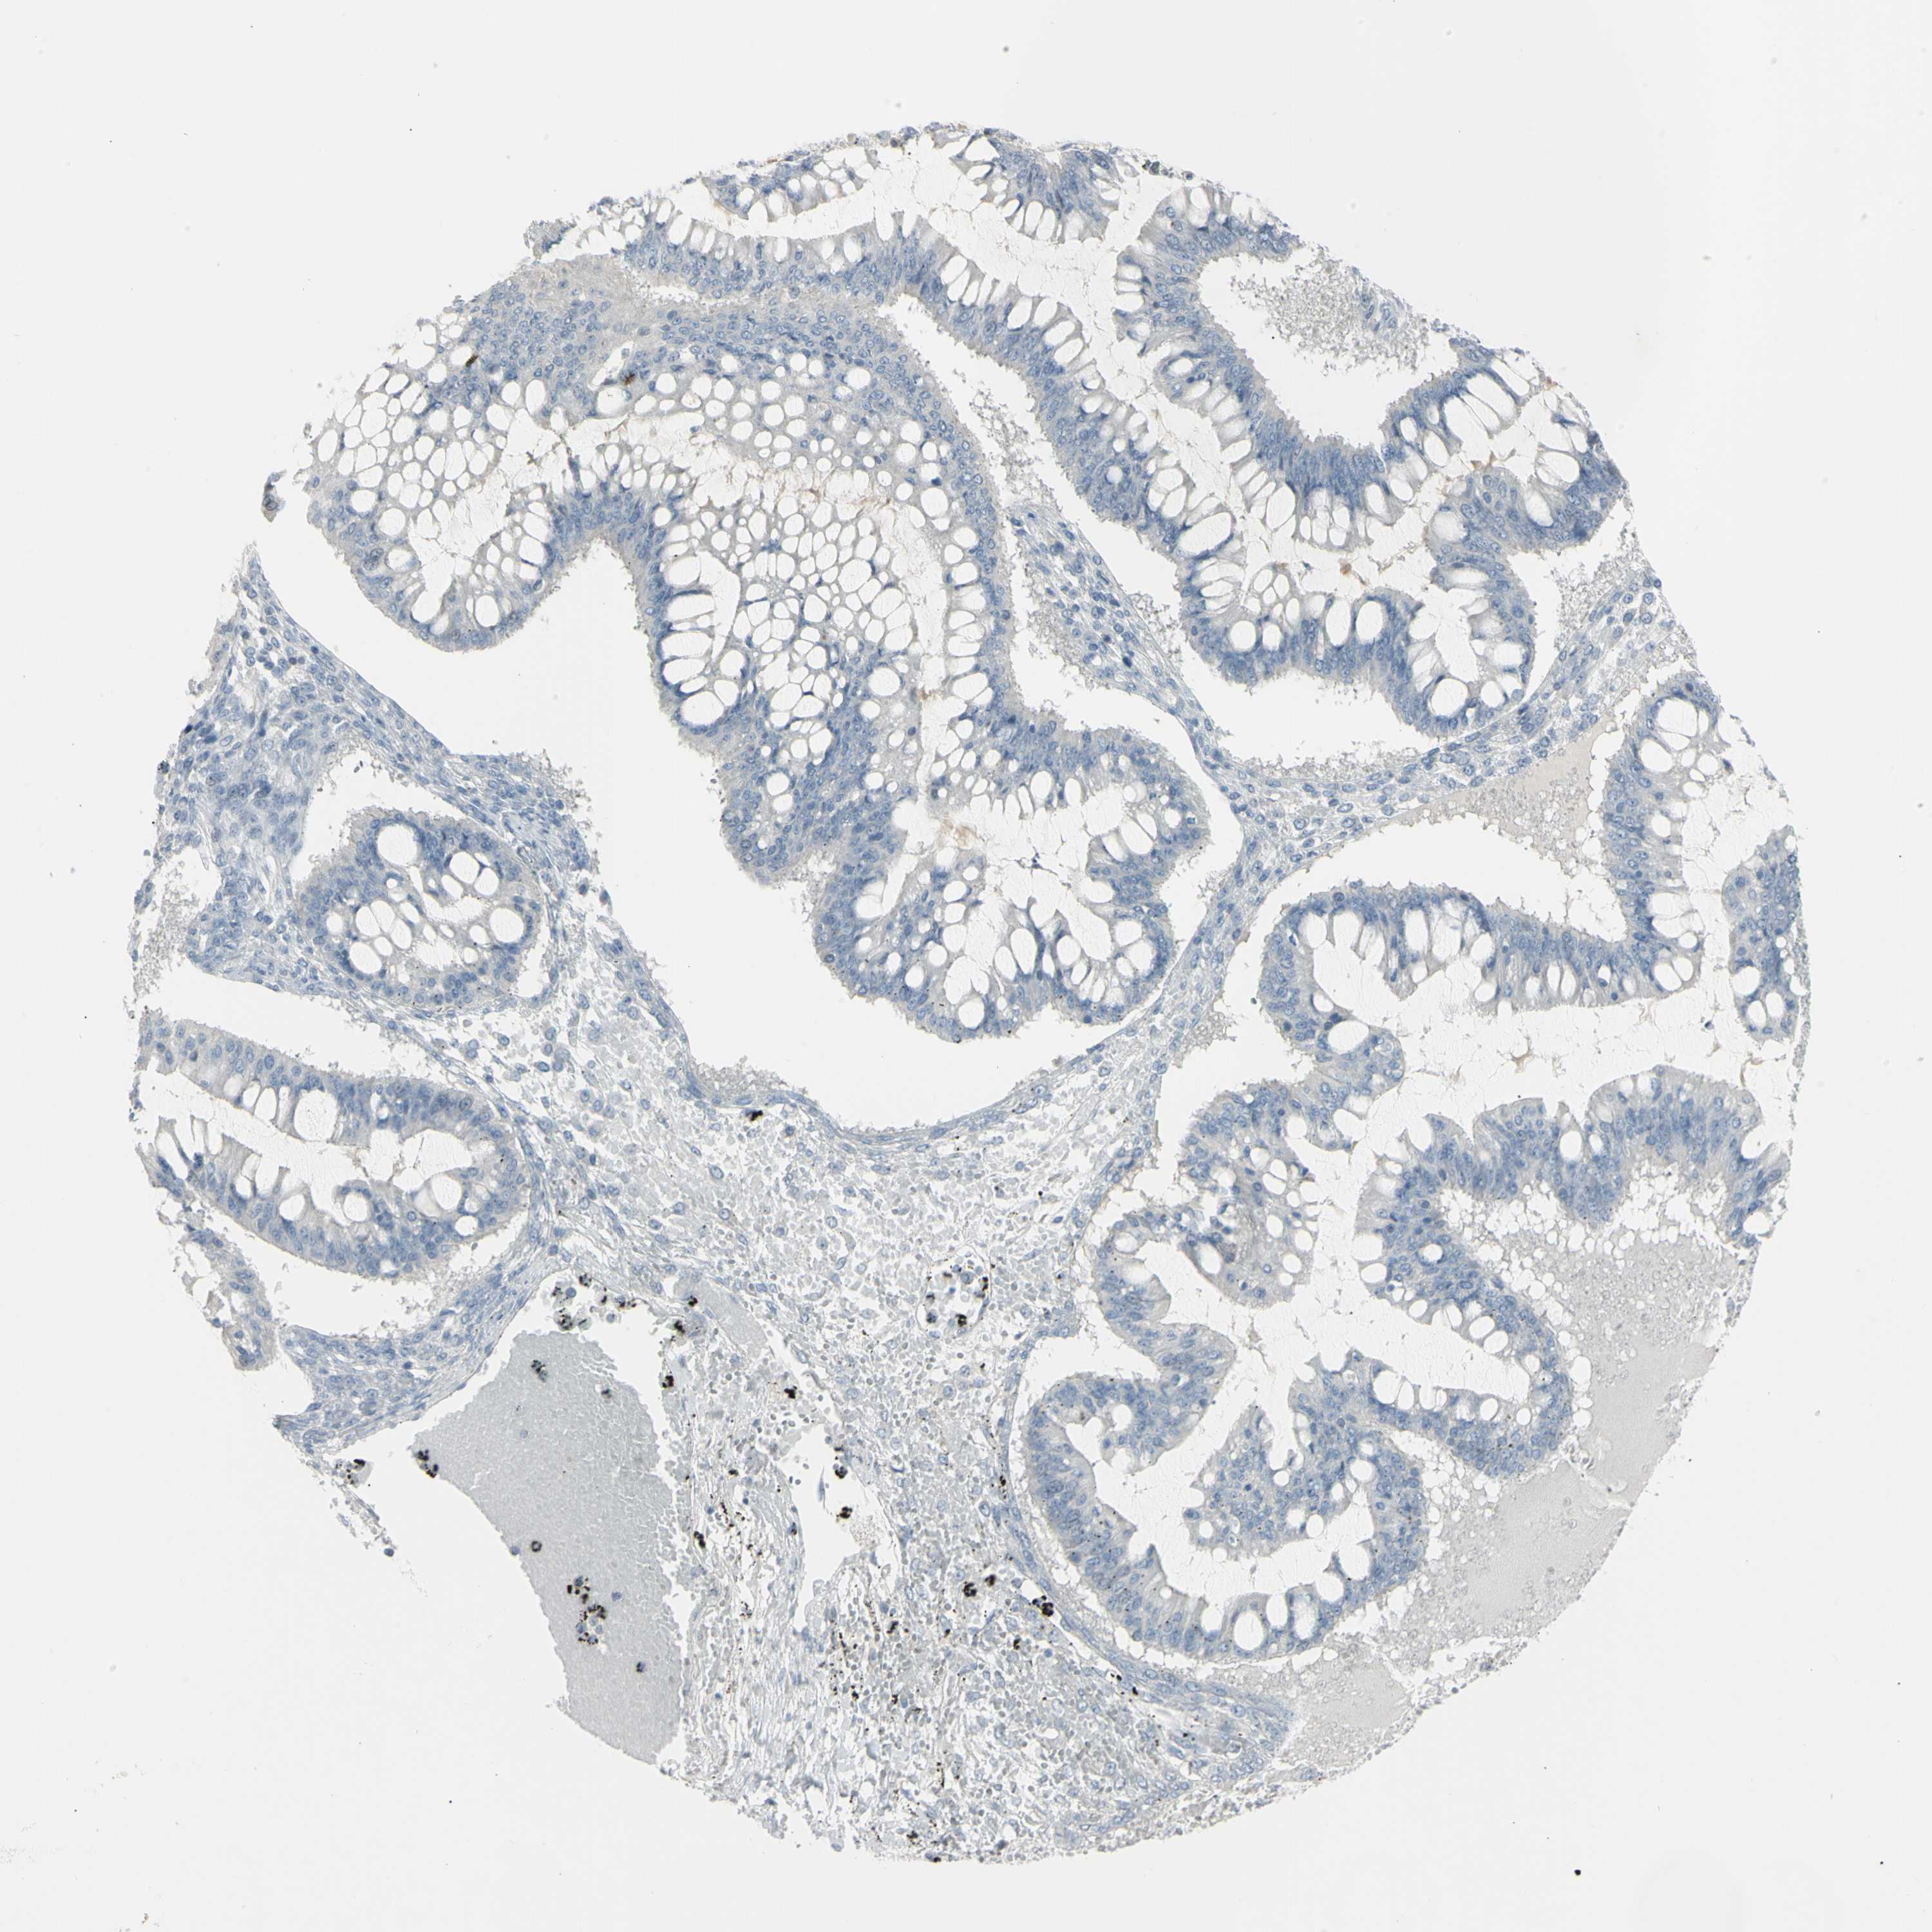

OVARIAN CANCER - Protein expressioni

A mouse-over function shows sample information and annotation data. Click on an image to view it in a full screen mode. Samples can be filtered based on level of antibody staining by selecting one or several of the following categories: high, medium, low and not detected. The assay and annotation is described here.

Note that samples used for immunohistochemistry by the Human Protein Atlas do not correspond to samples in the TCGA dataset.

Antibody stainingi

Antibody staining in the annotated cell types in the current human tissue is reported as not detected, low, medium, or high, based on conventional immunohistochemistry profiling in selected tissues. This score is based on the combination of the staining intensity and fraction of stained cells.

Each image is clickable and will lead to virtual microscopy that enables deeper exploration of all samples and also displays staining intensity scores, fraction scores and subcellular localization as well as patient and tissue information for each sample.

Antibody HPA009177

Antibody CAB002661

Cystadenocarcinoma, serous, NOS

Carcinoma, endometroid

Cystadenocarcinoma, mucinous, NOS

Carcinoma, NOS